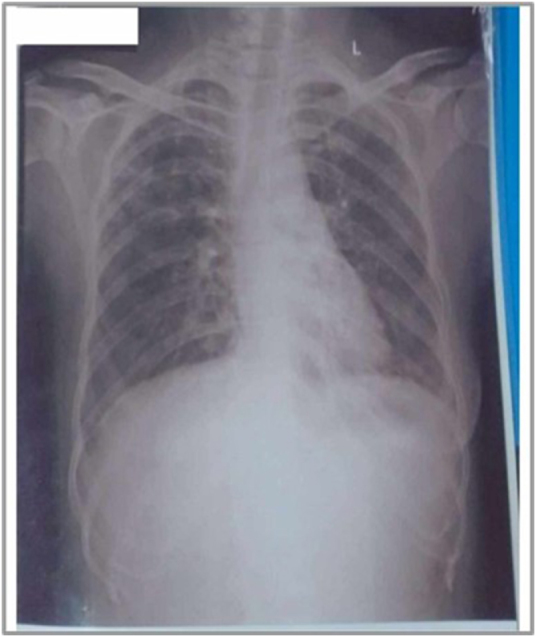

Case presentation: A 27-year-old woman receiving treatment for pulmonary tuberculosis presented to us with worsening joint pain, swelling, facial rash, and muscle weakness. She had trouble with basic movements like climbing stairs and noticed rashes over her face and knuckles. On examination, she had a malar rash and Gottron's papules, with noticeably weakness in her upper and lower limbs. Her lab results showed elevated ESR and a positive PM-Scl antibody; meanwhile, other autoimmune markers were negative. Her imaging revealed tenosynovitis and microvascular changes on capillaroscopy. She was then diagnosed with undifferentiated inflammatory arthritis, within the myositis spectrum - and was started on steroids and DMARDs while continuing her TB therapy.